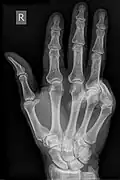

Acquired hand deformity refers to the structural or functional abnormalities that develop in the hand. There are multiple varying causes of acquired hand deformity, triggering significant consequences and complications. Trauma, including blunt force, penetrating injuries, burns, and sports-related incidents, is a primary cause of acquired hand deformities. Inflammatory conditions such as rheumatoid arthritis, gouty arthritis, and systemic lupus erythematosus can also contribute to hand deformities by affecting the joints. Degenerative arthritis, specifically osteoarthritis, functions to evoke impaired hand function due to the gradual deterioration of cartilage. Neurological disorders like cerebral palsy can result in hand contractures due to increased muscle tone and stiffness. There are different types of acquired hand deformities, each with distinct characteristics and underlying causes, such as boutonnière deformity, Dupuytren's contracture, gamekeeper's thumb, hand osteoarthritis deformity, mallet finger, swan-neck deformity, ulnar claw hand, among many others.